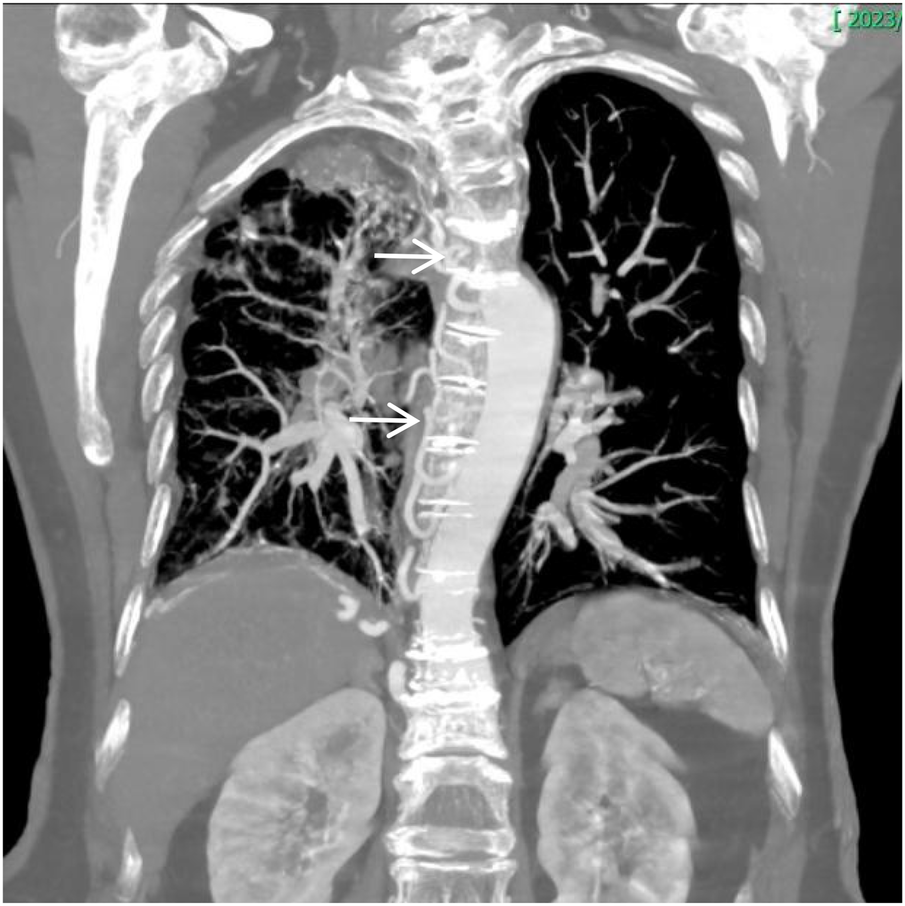

Figure 8

Coronal MIP image shows marked enlargement and tortuosity of the origins of the intercostal arteries on the right side of the thoracic aorta (white arrow).

Thoracoabdominal aortic CTA and chest CT findings are illustrated in Figures 1–14. There was no evidence of aortic dissection. The right pulmonary artery was absent distal to approximately 3 cm from the bifurcation, with a smooth and rounded defect margin. The main pulmonary artery and its major branches showed no abnormal densities. No right pulmonary artery branches were observed in the right lung. Multiple tortuous arterial branches from the right subclavian artery, descending aorta, and right renal artery supplied the right lung. The right hemithorax was smaller, with localized pleural thickening and adhesions bilaterally. Multiple bronchiectasis with thickened walls and patchy, nodular, and linear opacities encircled the right lung. Increased translucency and several hyperlucent regions were visible in the left lung. CT imaging findings demonstrated: 1. Congenital absence of the right pulmonary artery (RPA), with the right lung supplied by collateral circulation originating from the right subclavian artery, right intercostal arteries, and the right renal artery. 2. Right pulmonary hypoplasia, bronchiectasis of the right lung, accompanied by infection and partial consolidation in the right upper lobe, compensatory hyperinflation of the left lung, and multiple bullae in the left lung. 3. Bilateral localized pleural thickening and adhesions. 4. Osteoporosis and mild flattening of the T6 vertebra and compression fractures of T11 and T12.

Unilateral absence of the pulmonary artery (UAPA), or unilateral pulmonary artery agenesis, is a rare congenital condition caused by developmental malformation of the pulmonary vasculature. The condition often occurs together with congenital heart diseases, including atrial septal defect and tetralogy of Fallot. However, when it occurs without any other congenital heart defects, it is referred to as IUAPA, which is even rarer. Based on the data presented by Bouros et al. (2), the incidence of the condition is approximately 1 in 200,000, often presenting with right-sided predominance. However, relevant data from Chinese statistics is limited. Digital subtraction angiography (DSA) pulmonary angiography remains the gold standard for diagnosing IUAPA. A review of the existing relevant literature indicates that a significant proportion of reported cases have come from the discipline of ultrasound medicine in China (3, 4). However, CTA has gradually gained significance as a clinical examination technique in recent years. This is mainly due to the greater accessibility of CT equipment in comparison to DSA and its numerous advantages, which include rapid and easy application, minimal invasiveness, and its ability to simultaneously assess extravascular pathology (5). Using DSA or CT pulmonary angiography, the imaging typically reveals that the proximal segment of the affected pulmonary artery terminates in a smooth, rounded blind end, with non-opacified pulmonary trunk and distal branches. Due to the single functioning pulmonary artery, the main and contralateral pulmonary artery may appear dilated and tortuous. Extensive systematic collateral arteries develop from the systemic circulation, branching from vessels such as the aorta, intercostal artery, bronchial artery, subclavian artery, internal thoracic artery, internal mammary artery, phrenic artery, renal artery or coronary artery to supply the affected area. Aortic angiography is often used to visualize these systemic-to-pulmonary connections. In the presented case, the thoracic and abdominal aortic CTA clearly demonstrated the absence of the distal right pulmonary artery and the presence of a prominent collateral supply to the right lung from branches of bronchial artery, the right renal artery, right intercostal arteries, and right subclavian artery. Chest CT typically reveals a loss of volume in the affected lung, a shift in the trachea and mediastinum towards the affected side, asymmetric bronchovascular markings, and frequently, dilation of the contralateral pulmonary artery. It is also commonly accompanied by findings such as ipsilateral pneumonia, partial atelectasis, bronchiectasis, heterogeneous emphysema, and pulmonary bullae. The chest CT findings in this case are consistent with this description. During embryogenesis, the pathoanatomical features of UAPA include the development of the main pulmonary artery and the proximal segments of the right and left pulmonary arteries from the ventral portion of the sixth aortic arch. Conversely, the intrapulmonary arteries and their branches originate from the postbranchial pulmonary vascular plexus. If the central pulmonary artery is not fully developed or there is localized obliteration, leading to an inability to form the usual connections and communications with the intrapulmonary arteries, a congenital vascular malformation characterized by the absence of one or both pulmonary arteries is indicated. In the absence of one pulmonary artery, the affected lung is deprived of the blood flow necessary for its pulmonary circulation, which is a part of the dual pulmonary blood supply. Consequently, the affected lung is sustained by bronchial arteries or other systemic collateral vessels for perfusion, resulting in a poorer blood supply compared to the contralateral lung. This has severe consequences for pulmonary development, resulting in pulmonary hypoplasia and volume loss in the affected lung. In addition, hypocapnia develops in the alveoli and respiratory bronchioles as the affected lung's main blood supply comes from systemic arteries that have a low carbon dioxide content. Research has shown that this condition can lead to the triggering of bronchospasm, the reduction of pulmonary ventilation, the impairment of mucociliary clearance in the bronchial walls, and the subsequent occurrence of recurrent respiratory infections. It has been established that hypoventilation and hypoxia in the affected lung can induce pulmonary vascular wall thickening, vasoconstriction, and ultimately lead to pulmonary hypertension(PH) and even right heart failure. PH resulting from UAPA is classified as a form of “segmental pulmonary hypertension”, with a reported incidence ranging from 19% to 44%. Segmental pulmonary hypertension currently refers to a condition where diverse sources of pulmonary blood supply lead to distal pulmonary vascular disease, variably affecting different lung segments (6, 7). The collateral vessels supplying the affected lung are often dysplastic and prone to causing symptoms such as hemoptysis. The cumulative impact of these pulmonary pathologies leads to a variety of clinical and imaging presentations that resemble bronchiectasis, pulmonary tuberculosis, COPD, and pulmonary embolism, none of which are specific. This results in the prolonged misdiagnosis of the majority of patients with these prevalent diseases (8–10). The patient had received treatment for 30 years for diagnoses of pulmonary tuberculosis and COPD, with suboptimal therapeutic outcomes. During this period, multiple chest CT scans were performed; however, a comprehensive assessment of the pulmonary vascular system was not conducted, nor was the potential relationship between the long-standing recurrent pulmonary pathologies and pulmonary vascular developmental abnormalities considered. Instead, the absence of RPA was incidentally identified during CTA performed to investigate the cause of chest pain, with multiple systemic collateral vessels observed supplying the right lung. Concurrent echocardiography revealed no definite intracardiac structural abnormalities. Following a thorough review of the available evidence, the initial diagnoses were found to be consistent with the condition known as IUAPA. Hemoptysis is one of the primary clinical symptoms associated with this particular disease. Combined with chest pain and shortness of breath caused by pulmonary pathology, the clinical picture can resemble pulmonary embolism. Therefore, this disease should be differentiated from pulmonary embolism clinically. Acute pulmonary embolism often shows a significant elevation in plasma D-dimer levels. Although this patient had chest pain, it was ultimately confirmed to be caused by an osteoporotic vertebral compression fracture, involving an element of chance.Current management of this condition primarily focuses on symptomatic treatment, mainly aimed at preventing hemoptysis, infection, and PH. Early intervention in infants and young children through pulmonary revascularization of the affected lung may facilitate normal pulmonary development and reduce adverse outcomes such as PH.